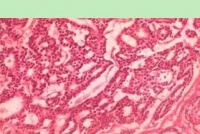

导管内乳头状瘤